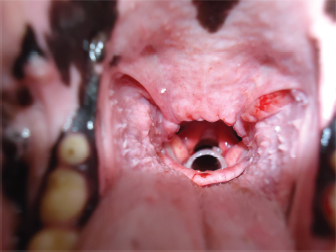

In dogs that showed an elongated soft palate, first palatoplasty was performed under general anesthesia and second placement of the silicone stent was performed as described above (Fig. 5), with the exception of the Brittany Spaniel where stent placement was only therapeutic due to costs of the palatoplasty surgery (Fig. 4). Two dogs (dog’s number 6 and 7) had prior to the laryngeal stent placement, a ventriculocordectomy through ventral laryngotomy, castellated laryngofissure, and palatoplasty because of laryngeal paralysis and elongated soft palate. The days after, the surgery normal respiratory sound was perceived, but the female Labrador Retriever coughed during water swallowing. Seven to ten days after the surgery, stridor relapsed in both the dogs. Laryngeal stenosis was confirmed in the glottis due to fibrosis reaction to the cordectomy. Thus, the laryngeal stent was placed for the treatment of the stenosis pathology and laryngeal paralysis. All dogs presented normal breathing sounds after the laryngeal stent placement. Case 1 was diagnosed with general megaesophagus and bronchopneumonia, regurgitation was constant, and euthanasia was performed for humanitarian reasons. The owners of dog’s number 1 and 2 decided the euthanasia several days after the laryngeal treatment for economic reasons of the diagnostic etiology and progressive weakness. In both the dogs, the stent was retrieved from the larynx, and mild inflammatory reaction was observed. Diagnosis, treatment, and survival time for each clinical case are summarized in Table 2.

Fig. 5. Correct position of the stent.